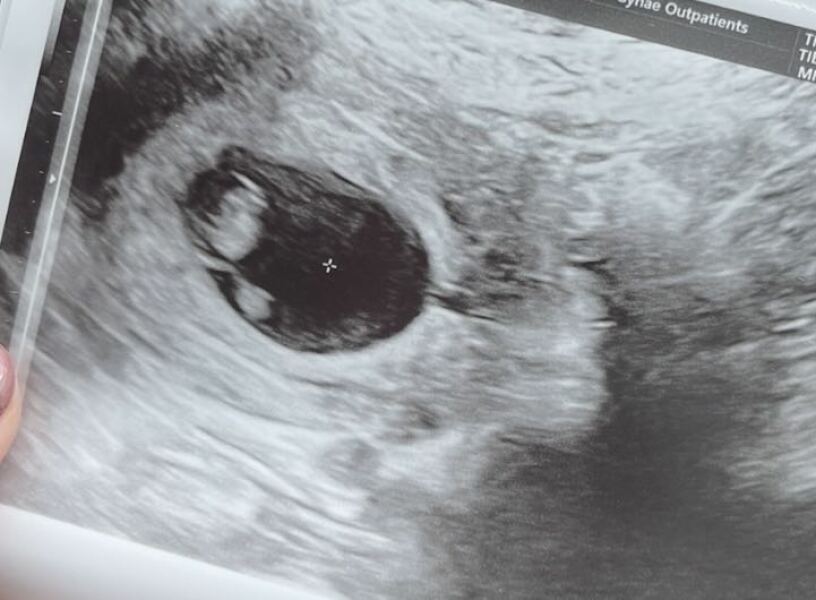

Over the moon with relief… measuring pretty much bang on from ovulation date at 7+4 and strong heartbeat seen… of course I’m still going to panic 🤣 but this is reassuring for now… private scan in a couple of weeks (had booked before EPU referral, and luckily managed to change date).

CustardCream31 · 17/03/2025 12:08